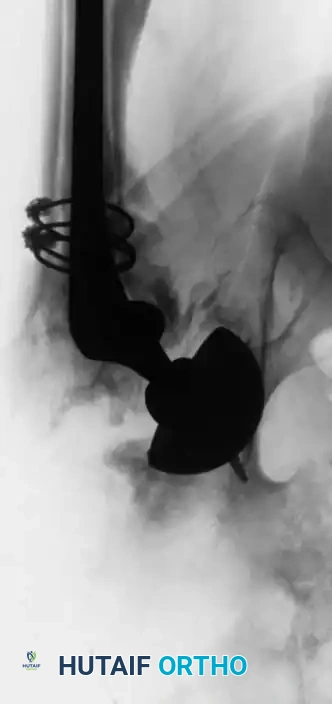

Late bleeding (≥ 1 week postoperatively) may occur secondary to a false aneurysm. In such cases, arteriography is required for the precise identification of the affected vessel, often followed by therapeutic embolization.